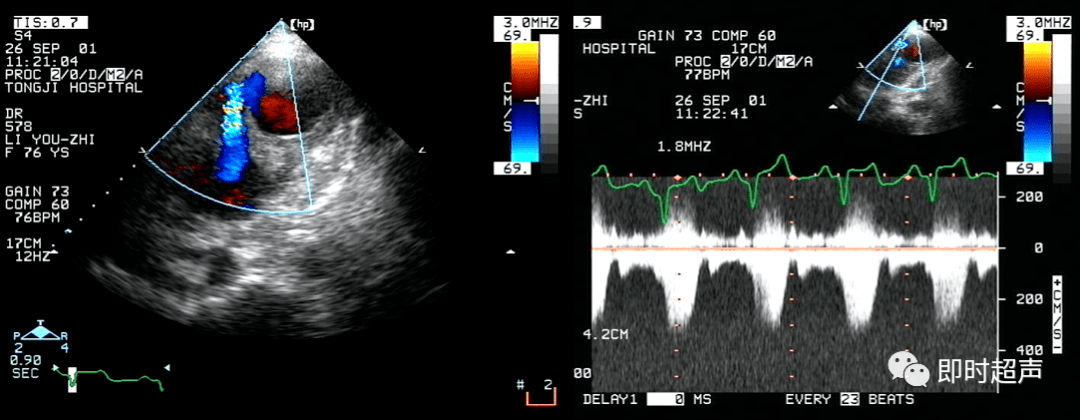

彩色多普勒血流显像(cdfi-3)右室流出道及肺动脉呈五彩镶嵌信号彩色